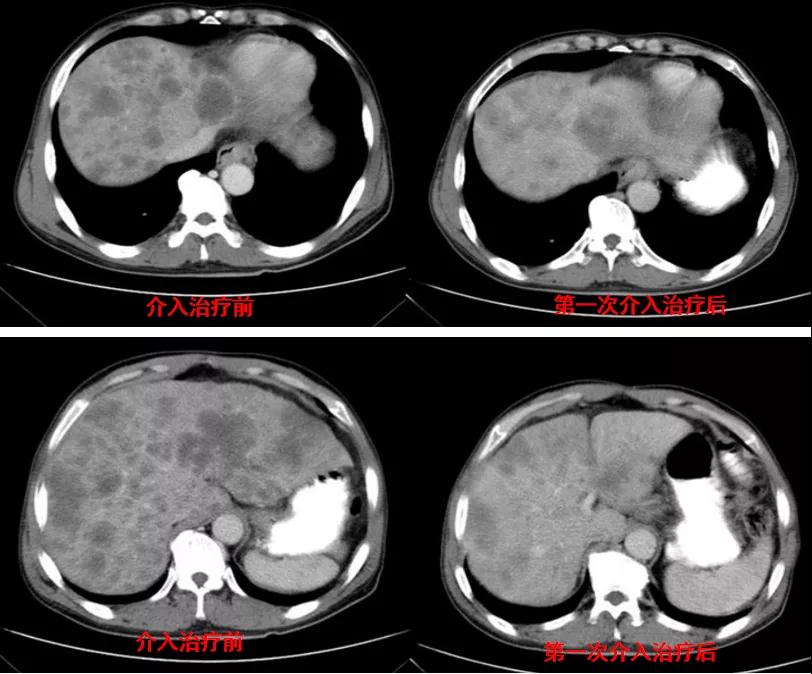

腹部CT检查(2020年11月10日):贲门胃底占位,肝内多发转移灶,腹主动脉旁多发淋巴结肿大,见图1。

图1